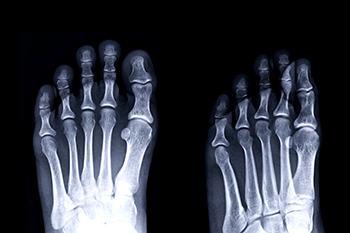

Symphalangism is a rare condition where the joints between certain bones are fused, limiting normal movement. In the feet, it often affects the toe joints, most commonly the middle joint of a toe, and results in stiffness and reduced flexibility. Causes may be genetic, as the condition is usually inherited, although it can also develop from abnormal bone growth. Symptoms include rigid toes that do not bend, discomfort while walking, difficulty finding comfortable shoes, and, in some cases, pain from pressure or altered gait. A podiatrist can help by evaluating the severity of the condition, recommending custom orthotics, providing supportive footwear advice, and offering treatment to reduce discomfort. If you have stiff or immobile toes, it is suggested that you consult a podiatrist who can accurately diagnose and offer relief solutions for what may be going on.